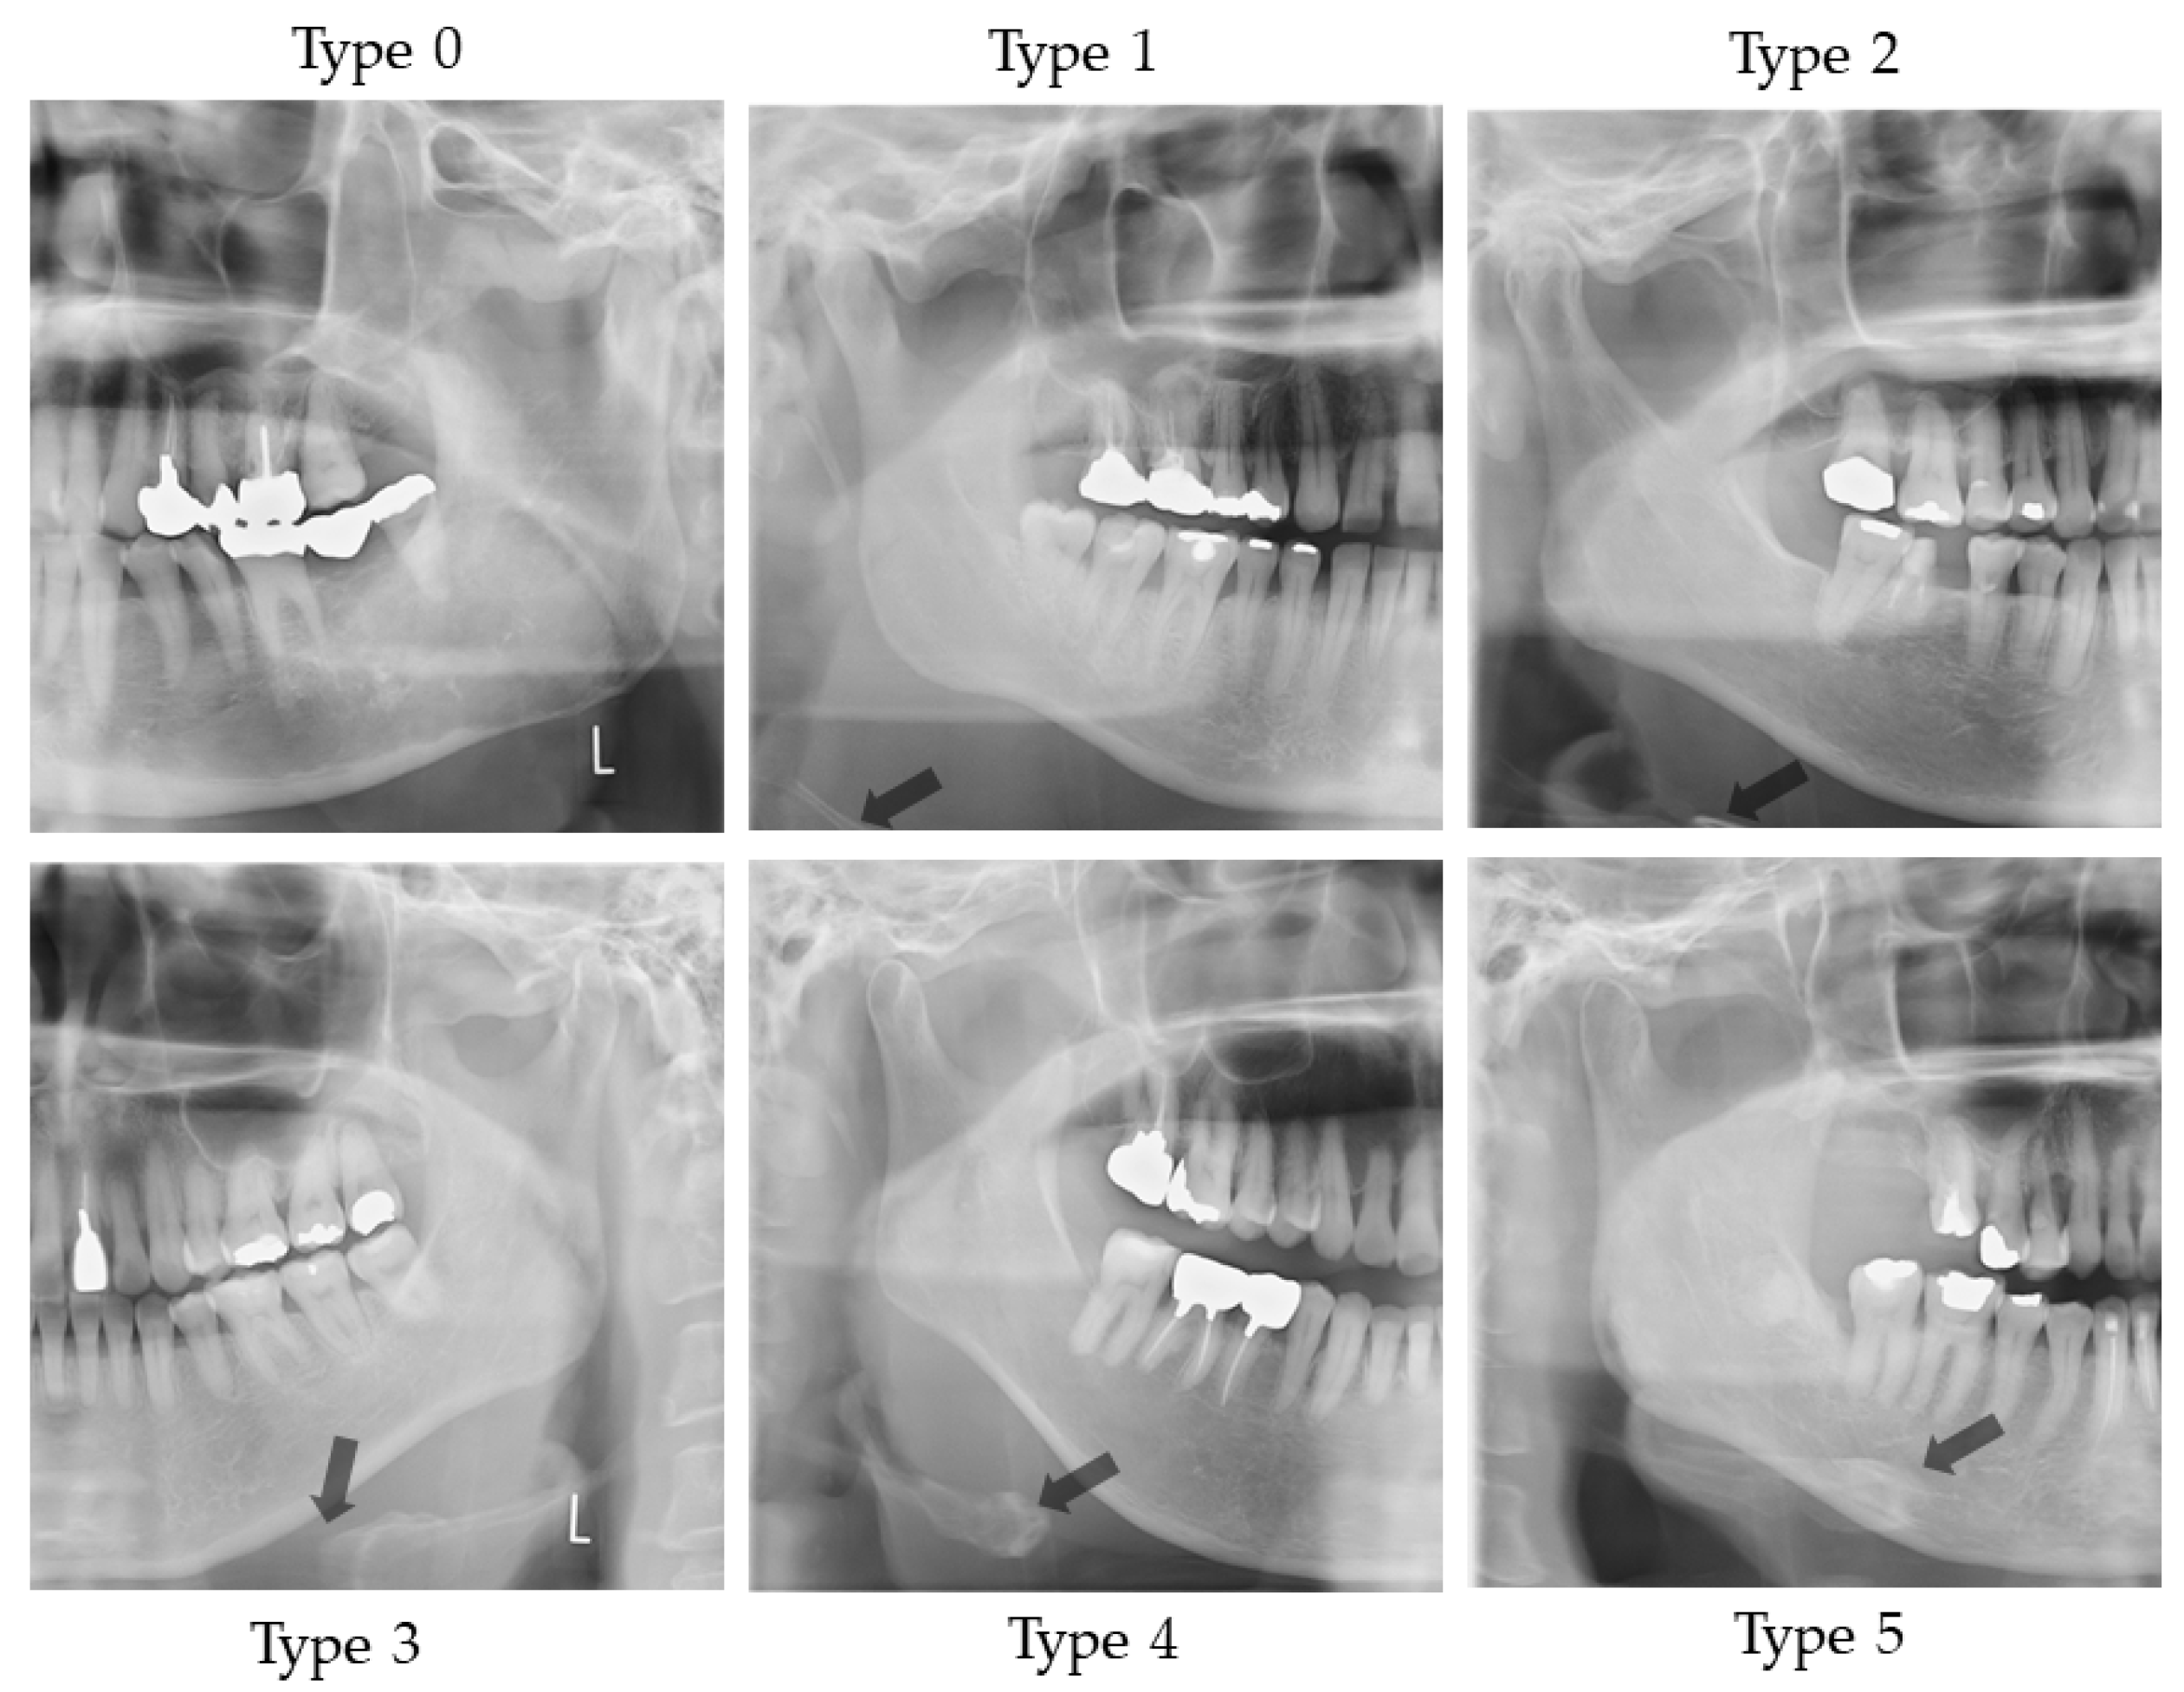

Figure 1 illustrates the evaluation of the vertical position of the hyoid bone and shows sample images. This method of measurement was as specified in Ito et al. [9]. Figure 2 shows sample images.

Vertical hyoid bone position. Mandibular border line was defined as a line that moves virtual line which is connecting the both side of mandibular angles, in parallel along the center line and attach to the lowest point of the mandibular inferior edge. An evaluation was conducted of the extent to which the hyoid body and greater horn appeared in the upper area from the mandibular border line.

Sample images of vertical hyoid bone position. Arrow shows the hyoid bone. On Type 0, hyoid bone is invisible.

Two landmarks were defined, as follows:

- The bilateral mandible line: A simulated line connecting the right and left sides of the angles of the mandible.

- The mandibular border line: The line that moved the bilateral mandibular line parallel to the lowest point of the lower border of the mandible.

An evaluation was conducted of the extent to which the hyoid body and greater horn appeared in the upper area from the mandibular border line. The following six groups were categorized:

Type 0: The hyoid bone could not be observed in the upper area from the mandibular border line;

Type 1: Only the greater horn was observed in the upper area from the mandibular border line;

Type 2: A less than half of the hyoid body was observed in the upper area from the mandibular border line;

Type 3: More than half and less than whole of the hyoid body was observed in the upper area from the mandibular border line;

Type 4: All of the hyoid body was observed in the upper area from the mandibular border line;

Type 5: The hyoid body overlapped with the mandible bone.

On the right and left sides, if the vertical position of the hyoid bone was different, the lower position side was recorded.